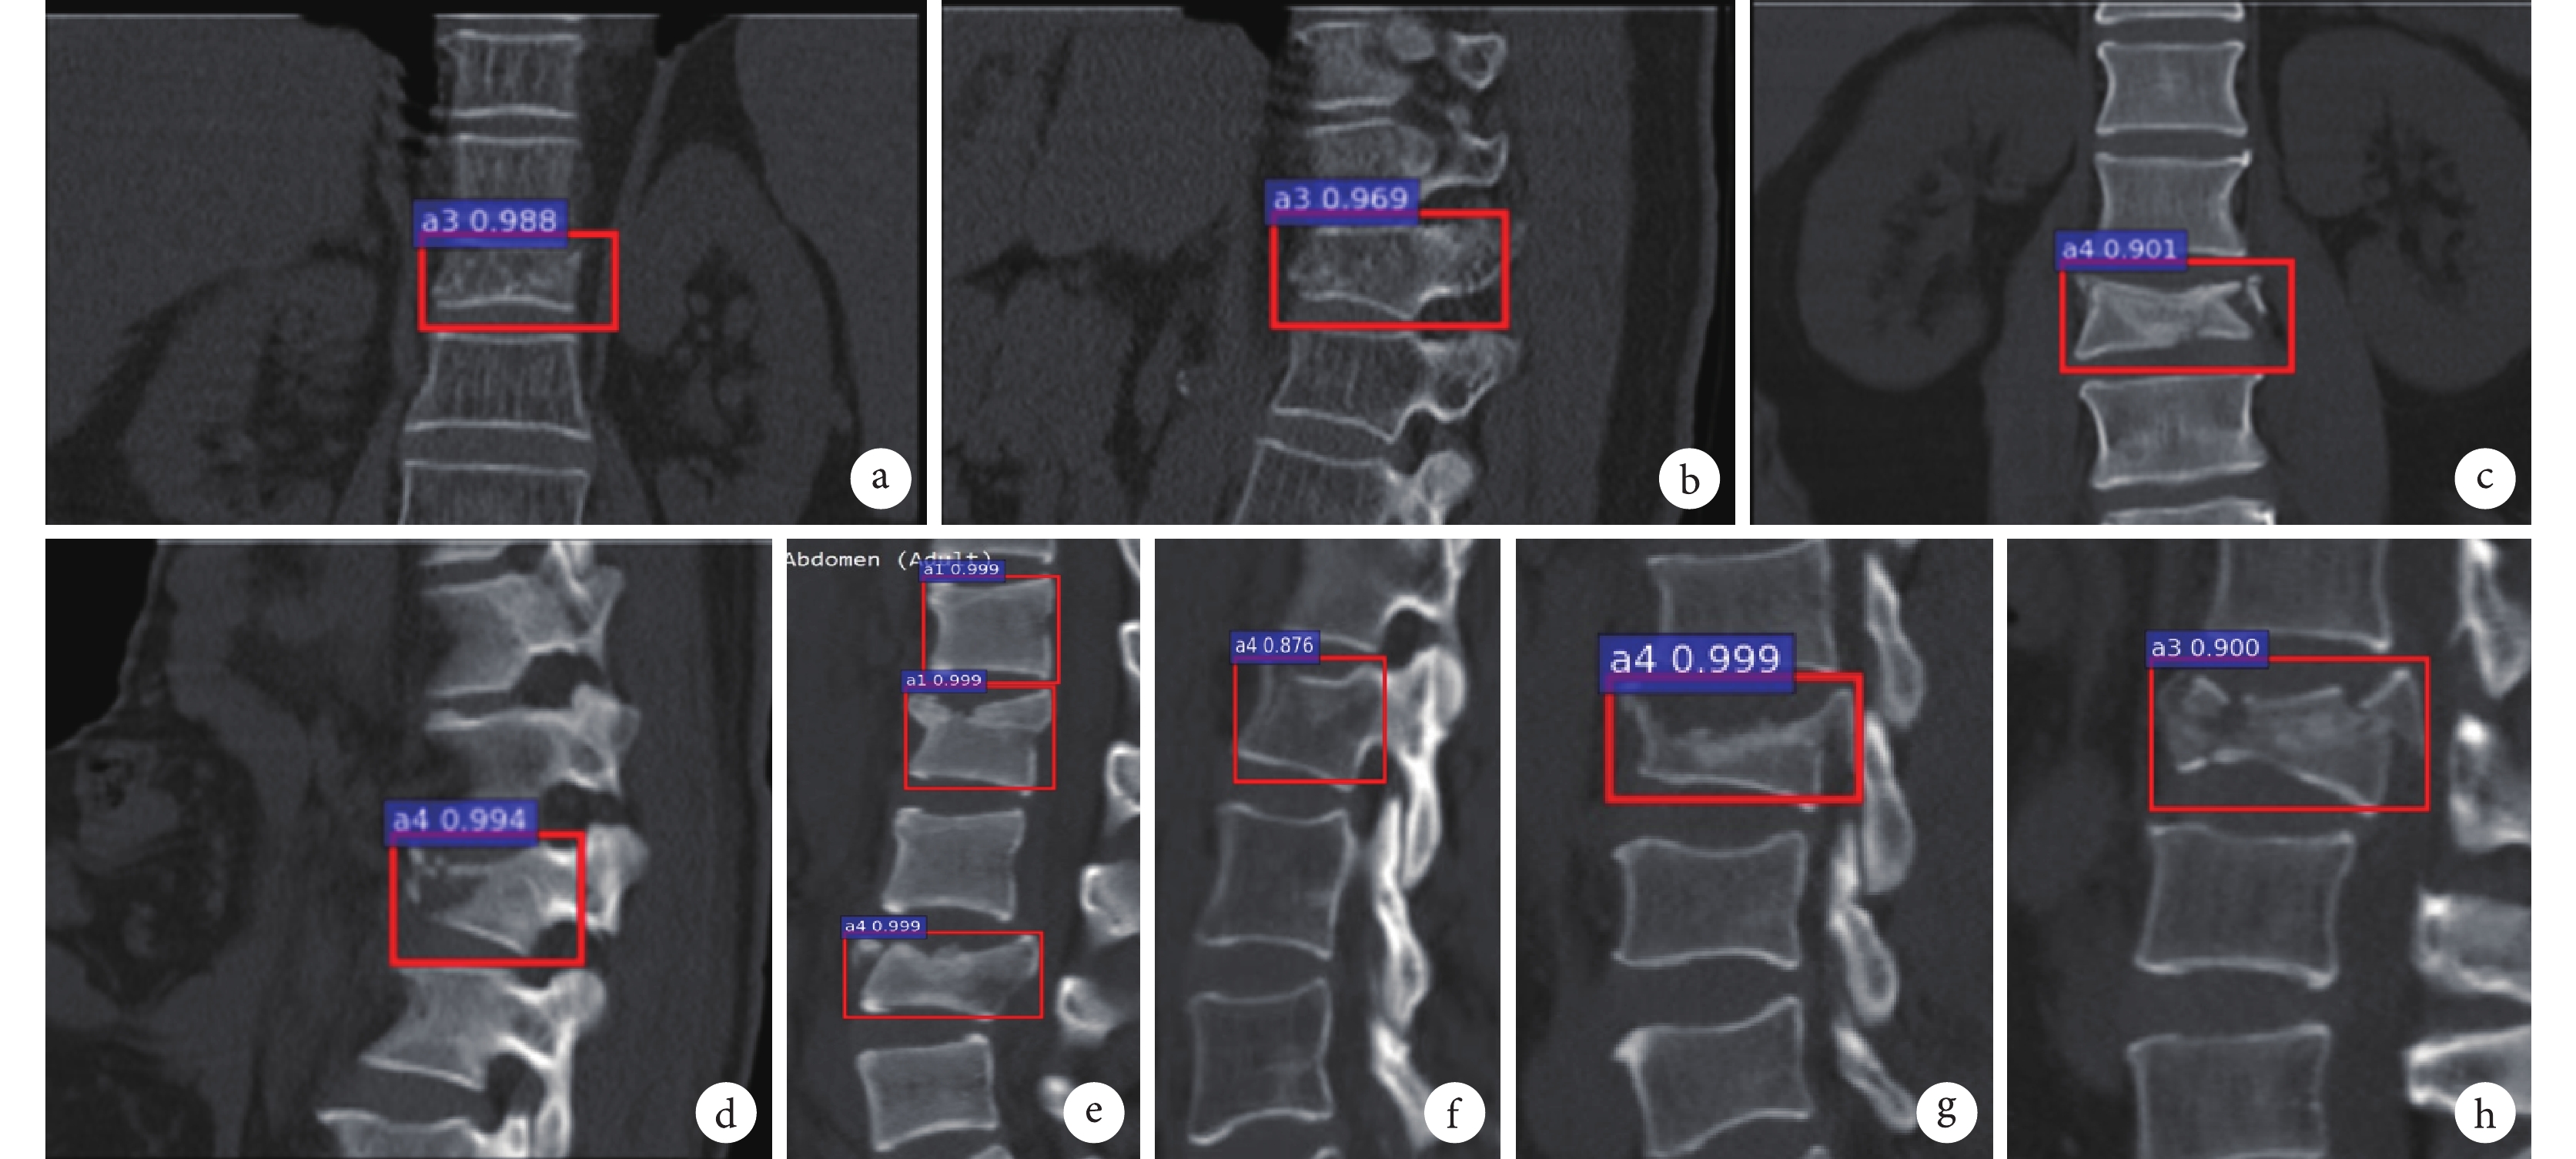

A型亞型智能分類結果如表3所示,在12張A1型骨折中,有1張沒有識別結果,1張錯成A4型,10張正確識別。在13張A2型骨折中,有4張錯識成A4型,9張正確識別。在38張A3型骨折中,1張無識別結果,2張錯識成A4型,35張正確識別。在41張A4型骨折中,有3張沒有識別結果,1張錯識A3型,37張識別正確。該分類的總體正確率為87.5%,Kappa系數為0.817(P<0.001)。表4為根據該結果計算出的單類正確率、靈敏度、特異度、陽性預測值、陰性預測值和約登指數。圖6為成功識別與錯誤識別示例。圖7為A型亞型分類訓練過程中損失值與迭代次數的關系。

a. 正確識別A3型(冠狀位);b. 正確識別A3型(矢狀位);c. 正確識別A4型(冠狀位);d. 正確識別A4型(矢狀位);e. 正確識別A1、A4型(矢狀位);f. 將A1型錯識為A4型(矢狀位);g. 將A3型錯識為A4型(矢狀位);h. 將A4型錯識為A3型(矢狀位)